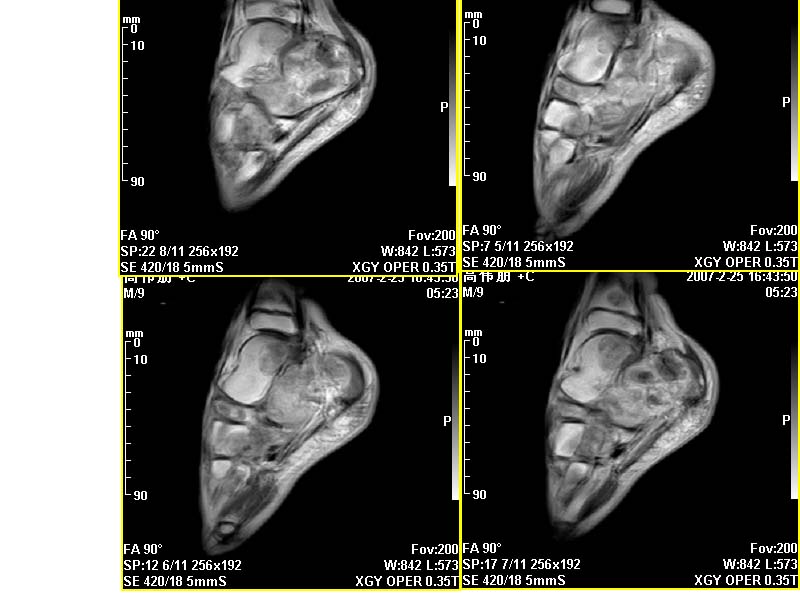

m,9y,左足肿痛半年,无皮肤发红,诱因为外伤后起因。无发烧,无其他疾病。临床考虑多发血管瘤。mri增强后有强化,请分析。是骨髓瘤吗?

左足多发囊状膨胀性骨质破坏,边较清,关节间隙及软组织未见明显异常。结合临床。可排除炎症性病变。病变中心为骨髓腔。有强化。中心坏死。嗜酸性肉芽肿可能大。

今天从天津肿瘤医院传来消息:病理结果是非骨化性纤维瘤。

平片也诊断不了,这种非骨化性纤维瘤实在是太罕见了,如果资料全,病理可靠,可以作一个病例报道了。